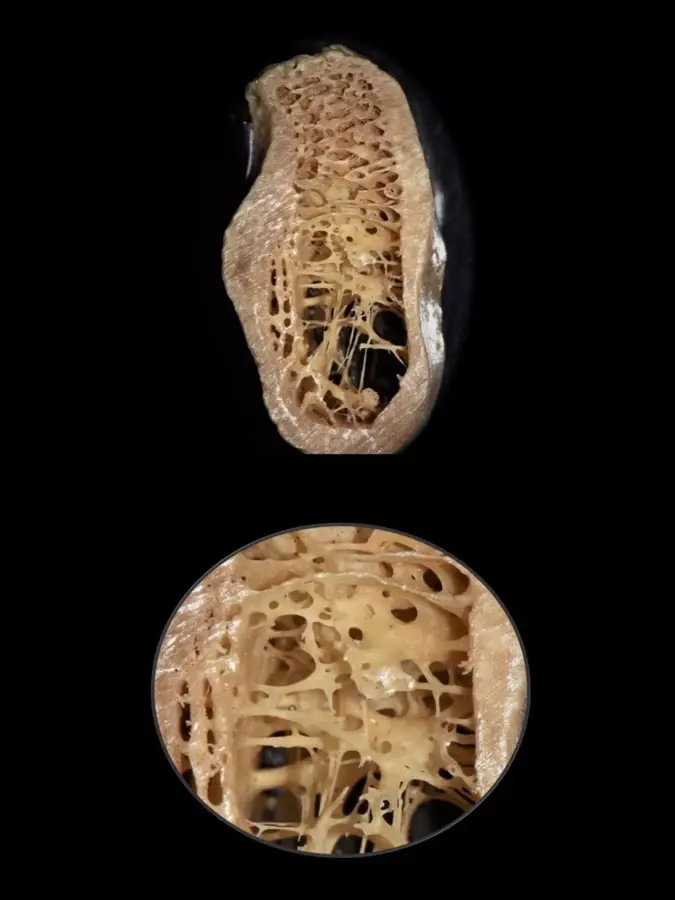

Durante años, se establecieron las propiedades biomecánicas del hueso basándose únicamente en medidas a gran escala, pudiendo diferenciarse entre el hueso trabecular y el hueso cortical. Sin embargo, actualmente es posible un mayor análisis a nivel micrométrico que permite explorar entre los componentes orgánicos, tisulares, celular y moleculares. Es así que gracias a aproximaciones nanoestructurales se muestran asociaciones entre las propiedades biomecánicas y las calidades óseas, las que se pueden presentar tanto en el hueso cortical como en el trabecular de manera indistinta. En el cortical, el espacio poroso ocupa el 5-10%, mientras que en el trabecular se encuentra en el 30-90% del total de la estructura9 (Figura 1).

En base a estudios realizados en biomodelos, consideramos que es importante, además de los clásicos parámetros, analizar el grosor de las trabéculas óseas y las dimensiones de los espacios medulares, ya que juegan un rol determinante en la calidad y dureza del hueso.

Por ejemplo, se dice que el sector anteroinferior de la mandíbula suele presentarse hueso tipo I y en el posteroinferior tipo II. La variante en la zona posterioinferior mandibular se debe a que, a pesar de tener una buena cortical ósea y cantidad de hueso esponjoso, la dimensión de los espacios medulares es muy amplia y el grosor de las trabéculas tan finas como el espesor de un cabello11 (Figura 3).